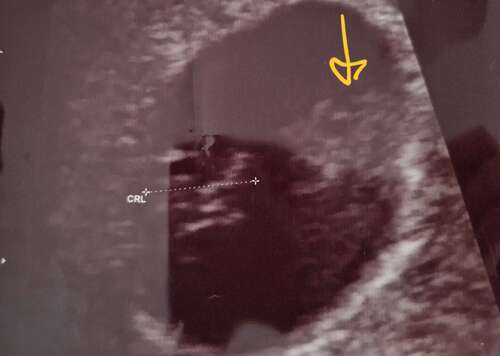

Hier mijne van afgelopen maandag ❤️ Vraag mij alleen af wat dat "dingetje" erboven is..zij wist het zelf niet echt te zeggen. Heb wel al een aantal dagen roze/bruine afscheiding. Ze zij dat dat misschien een wondje ofzo kon zijn met bloed ? Iemand een idee? Of herkenning??